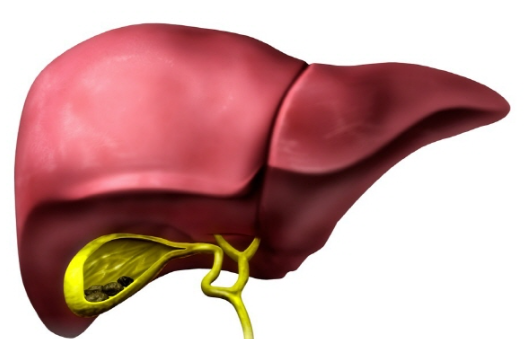

담낭염은 담낭의 벽에 염증이 발생하는 질환으로, 이는 대부분 담석증 때문에 발생합니다. 담석증이란 담즙에 포함된 콜레스테롤이나 빌리루빈 같은 물질이 응고되어 돌처럼 굳어진 상태를 말하며, 이러한 담석이 담낭의 출구를 막게 되면 담즙이 제대로 배출되지 못하고 담낭 내에 고이게 됩니다.

이 상태가 지속되면 담낭 내부의 압력이 증가하게 되고, 이는 결국 염증을 유발하게 됩니다. 염증이 진행됨에 따라 담낭 벽이 두꺼워지고, 이 상태가 심해지면 감염으로 이어질 수도 있습니다.